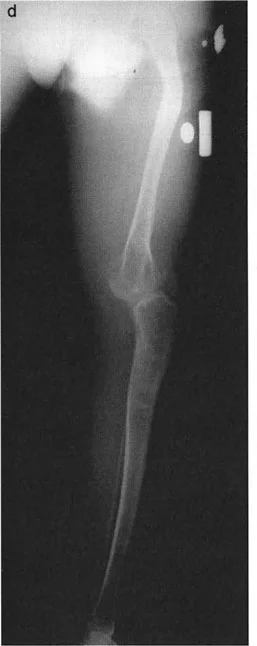

- الأشعة السينية الطويلة للطرف السفلي بالكامل أثناء الوقوف (Standing Long-Leg AP View): تُعد هذه الأشعة حاسمة لتقييم المحاذاة الميكانيكية للطرف السفلي بأكمله. تُظهر بدقة درجة الانحراف الأفحج (Varus) أو الأروح (Valgus) وتساعد في تحديد مركز دوران التشوه (CORA).

- الأشعة الجانبية الطويلة للطرف السفلي بالكامل أثناء الوقوف في أقصى بسط (Standing Long-Leg Lateral View in Maximum Extension): تُستخدم لتقييم تحدد حركة الركبة (FFD) والركبة الارتدادية (Recurvatum)، وتحديد ما إذا كان التشوه عظميًا أو ناتجًا عن تقلص في الأنسجة الرخوة.

- التشخيص الدقيق: يجب تحديد ما إذا كان تحدد الحركة ناتجًا عن تشوه عظمي (تقوس أمامي في الفخذ أو الساق) أو تقلص في الأنسجة الرخوة (الأوتار الخلفية، محفظة المفصل).

- التشخيص: يجب تحديد ما إذا كانت الارتدادية عظمية (تقوس خلفي في الفخذ أو الساق) أو ناتجة عن رخاوة في الأنسجة الرخوة أو ضعف عضلي.